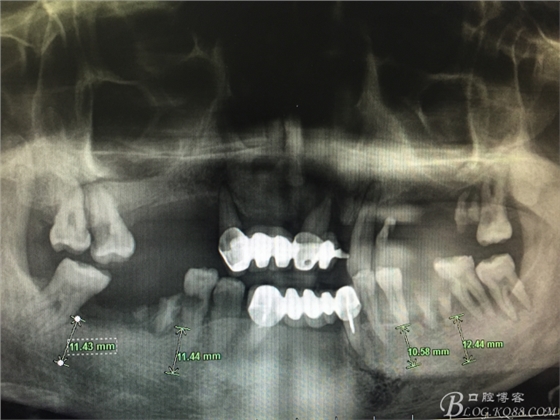

患者37歲 男 全口牙周病 手術(shù)一次完成 全程3小時全口種植修復(fù)全口種植修復(fù)全口種植修復(fù)全口種植修復(fù)全口種植修復(fù)全口種植修復(fù)全口種植修復(fù)全口種植修復(fù)全口種植修復(fù)全口種植修復(fù)全口種植修復(fù)全口種植修復(fù)全口種植修復(fù)全口種植修復(fù)全口種植修復(fù)